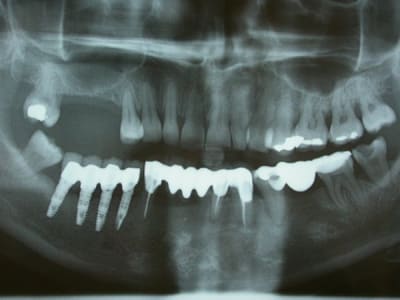

Franchement je pense que Ziyou a trouvé.

Je vais faire le forcing pour qu'elle rentre plus tôt de congés afin de virer cette 38.

Bon, tout s'est accéléré, le gonflement, la douleur...

Elle est revenue et j'ai avulsé la 38 (elle commençait à être douloureuse!)

Elle a une belle cellulite. Je pense qu'il était grand temps de virer cette 38. L'odeur était magnifique.

J'ai une patiente qui est en cours de soin et à qui j'ai fait une ordonnance pour une pano. Au dernier RDV, elle est venu avec sa pano, je découvre une grosse lésion apicale sur la 46, totalement asymptomatique. D'apres ce qu'elle m'a dit, cette dent ne lui a jamais fait mal. Je lui explique qu'il faut extraire la dent. Normalement, le RDV pour l'extration est prévu demain dans l'apres midi.

Mais lundi, elle est venue au cabinet en urgence car elle a fait un abces sur cette dent. Ma titulaire l'a mis sous ATB, sous amoxicilline. Je me pose la question, est ce que j'enleve la dent ou je reporte le RDV. Cela fera 4jours seulement d'ATB. D'apres ce que j'ai appris à la fac, il faut normalement attendre une semaine avant de réintervenir sur la dent